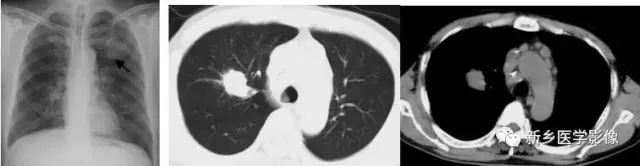

渗出性病变X线及CT图像

胸部X线正位片(a)示左肺纹理增多、模糊;CT肺窗(b)和纵膈窗(c)示两下肺片状高密度影,边缘模糊。